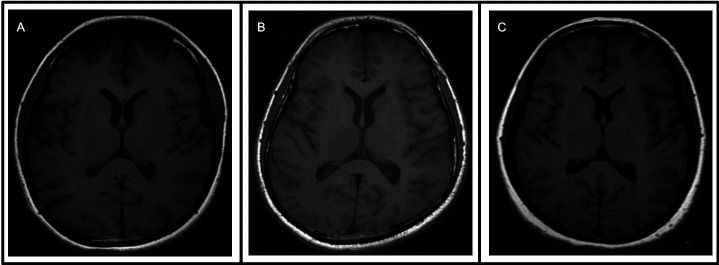

Results: We described the clinical, microbiological, radiological and serological features of five patients with a TBM-like presentation eventually diagnosed with MOG-associated meningitis. Symptoms included headache, vomiting, visual impairment and weakness. Three patients showed normal MRIs and two patients showed MRI findings consistent with demyelination. Serum MOG antibody testing was positive only on serial testing of all five patients. The final diagnosis was MOG-associated meningitis in two patients and MOG-associated meningoencephalitis in three patients.

Abstract Image